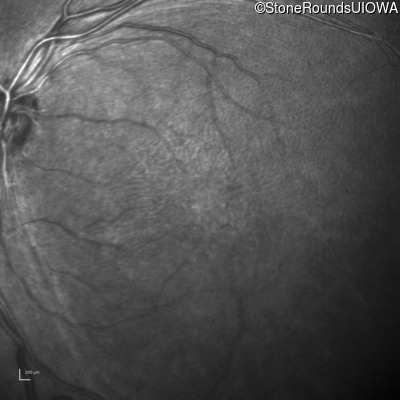

Infrared Fundus Photograph - Right - 10/40

Exemplar